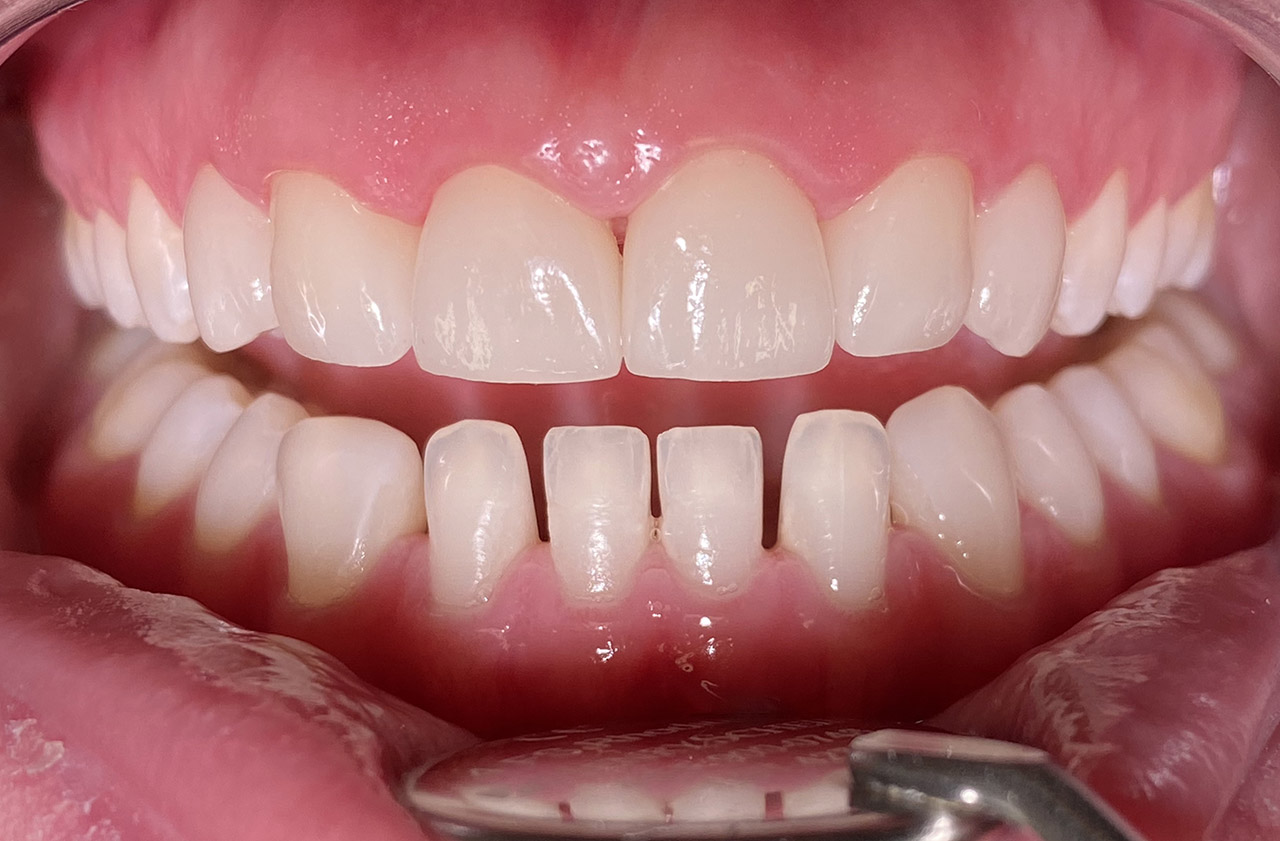

Traumatologie

Zahn 11 nach Sturz frakturiert, Pulpa nicht eröffnet, Zahnstück adhäsiv wiederbefestigt, Zahn konnte vital erhalten werden.

Vorher Nachher

Vorher- / Nachher-Vergleich mit Slider